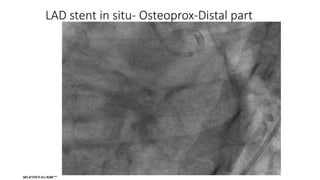

LAD stent in situ- Osteoprox-Distal part

LAD stent insitu- Osteoprox-Distal part